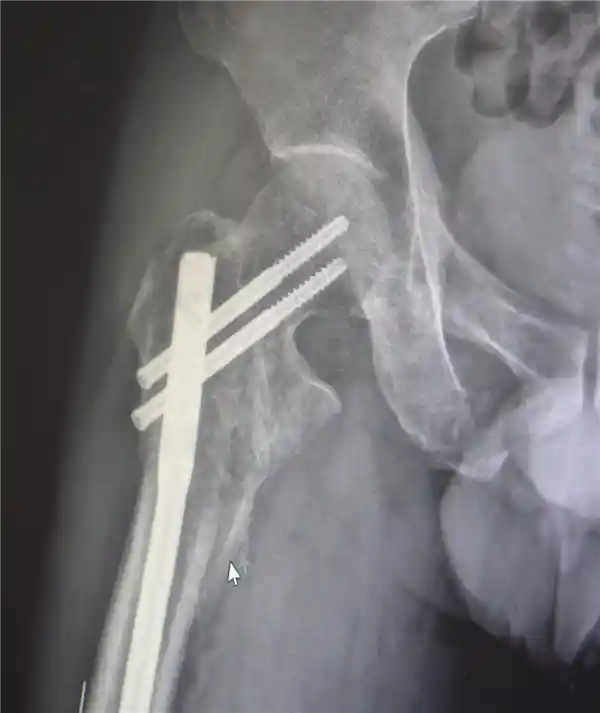

创伤性失血性休克、多发性肋骨骨折、肺部损伤、右侧肩胛骨粉碎骨折、右侧肱骨髁上开放粉碎性骨折、右股骨粗隆及股骨干粉碎性骨折、骨盆粉碎性骨折、腰椎横突多发骨折、腰骶柱神经损伤、臂丛神经损伤、胸腔积液、腹腔积液等。

经医生检查,张先生身上共有六个主要骨折部位,其中多数为严重的粉碎性骨折,全身骨折碎片超过30块。

最终医疗团队运用了类似修复古董瓷器的“拼古董”复位固定技术,先将大块骨片进行拼接,再处理小块碎片,先后实施了两次手术。

部分手术后拍摄的影像